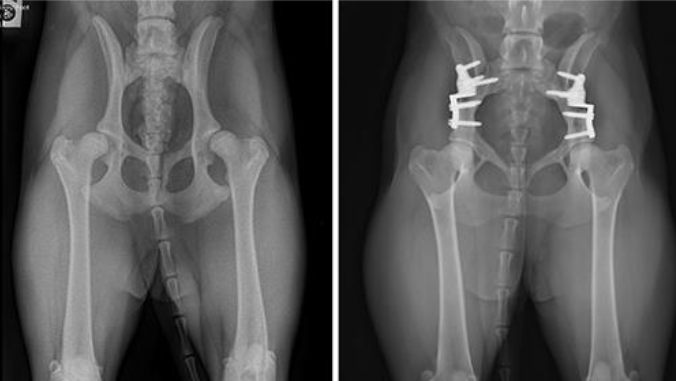

Double Pelvic Osteotomy and Triple Pelvic Osteotomy in Dogs

Double pelvic osteotomy (DPO) and triple pelvic osteotomy (TPO) are very similar in concept to Juvenile Pubic Symphysiodesis (JPS). With DPO/TPO the pelvis is cut (with a saw) so that the socket can be rotated over top of the ball portion of the joint to provide more coverage to the ball. Hence, the ball is prevented from sliding (partially) out of the joint. The difference between DPO/TPO and JPS is that with JPS this coverage of the ball is increased gradually over time, and with double pelvic osteotomy (DPO) and triple pelvic osteotomy (TPO) this is achieved immediately.

Dogs that are candidates for double pelvic osteotomy (DPO) and triple pelvic osteotomy (TPO) are typically young, about 5-11 months of age (approximately). Really, a dog is a candidate if the hips are well formed, and there is no osteoarthritic change yet, but the hips are loose (lax) and we know those dogs are at risk of developing osteoarthritis later in life.

Double and triple pelvic osteotomy are named as such because the pelvis is cut (osteotomized) either in 3 places (triple) or two places (double) in order to rotate that socket (one socket) over the ball. Triple pelvic osteotomy is the older way of doing it, double pelvic osteotomy has been used since 2006. In Dr. Franklin’s opinion, the evidence and experience show this is a really good hip dysplasia surgery for dogs that are good candidates, but the challenge is appropriately identifying patients that are good candidates. Many dogs already have osteoarthritic change and cartilage wear of the hips by the time they are diagnosed and hence are not candidates.

Dog with bilateral, staged double pelvic osteotomy (pre-operative and 8 weeks post)